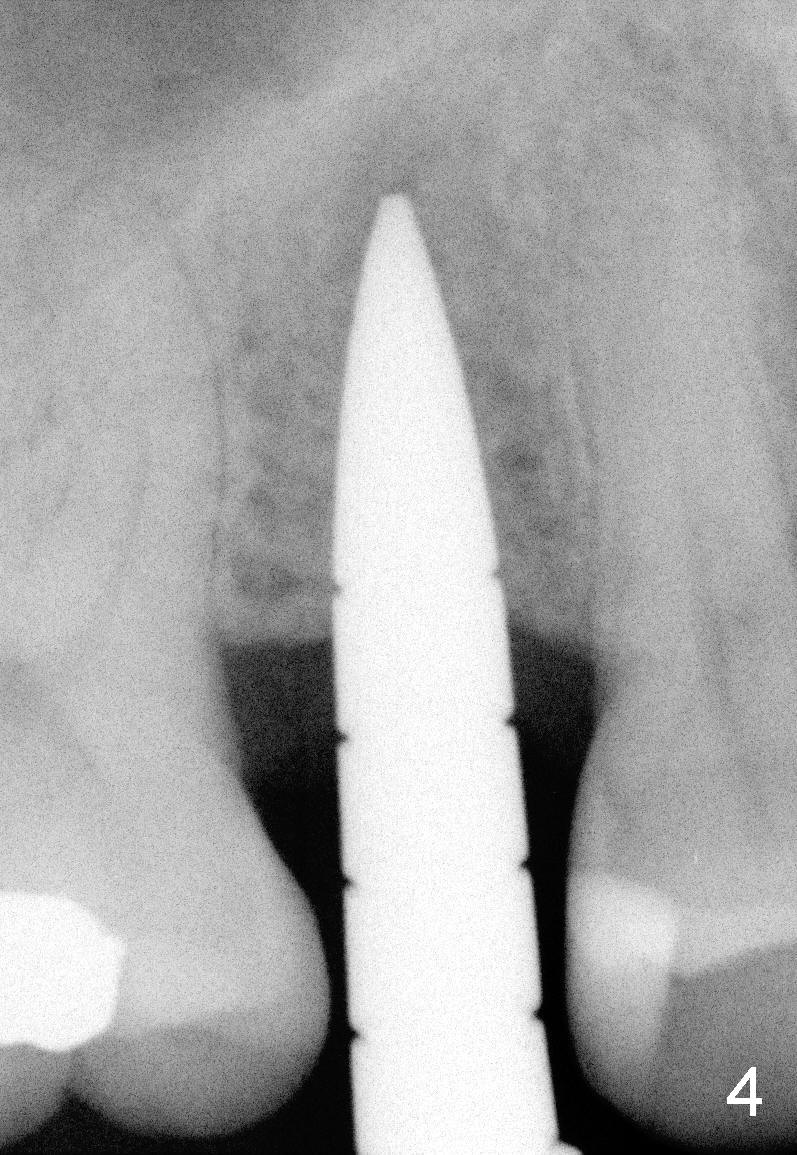

The tooth #4 was removed from a 41-year-old man (Fig.1). Fig.2 was taken 1 year and 7 months post extraction. Osteotomes (Fig.3,4) were used to create osteotomy (7 yr 9 m post ext). A 4x14 mm implant was placed below the sinus floor with insertion torque > 60 Ncm (Fig.5). The surgery was flapless (Fig.6). No antibiotic was taken pre- and post-op. The implant was found to be tender and loose. It was removed without bone graft.